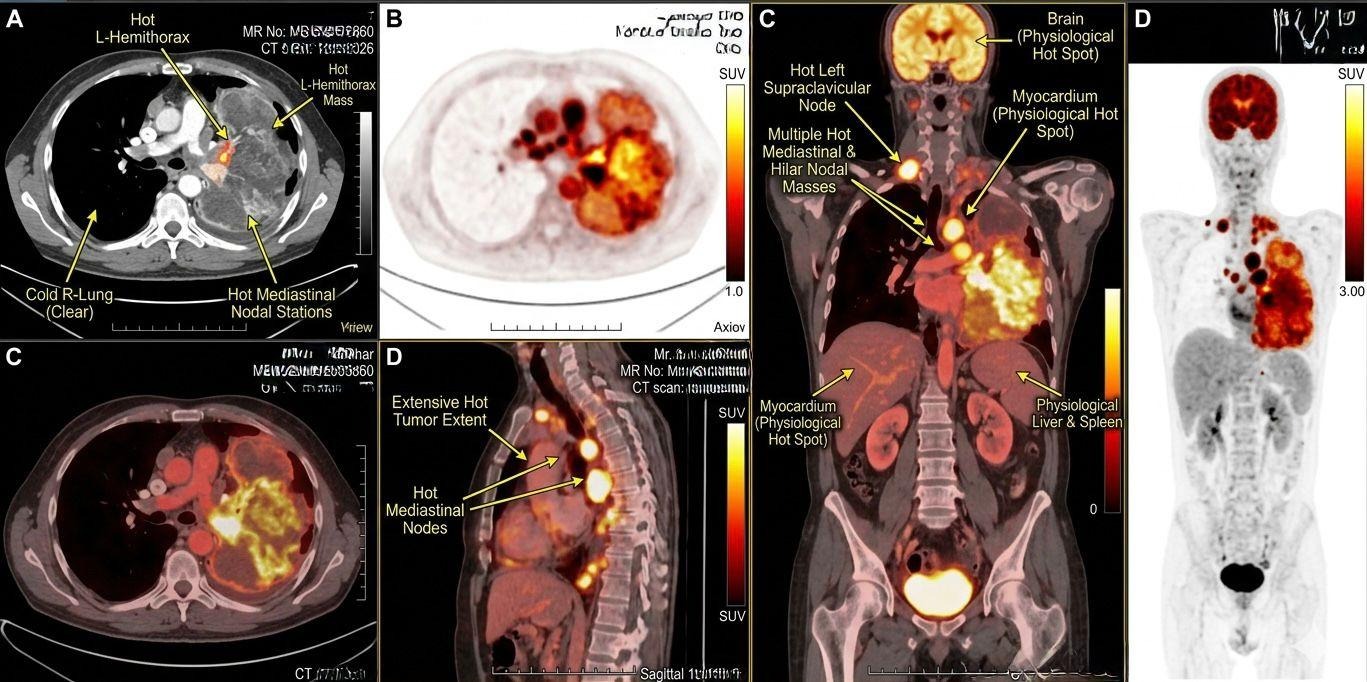

Functional Metabolic Profiling

Whole-body fluorodeoxyglucose positron emission tomography integrated with computed tomography demonstrates intense radiotracer uptake with markedly elevated standardized uptake values, reflecting heightened glycolytic flux and tumor metabolic reprogramming. An extensively hypermetabolic bulky mass occupies the entire left hemithorax, in sharp contrast to the metabolically inactive right lung, confirming a dominant unilateral primary malignancy. There is widespread lymphatic dissemination with multiple avid mediastinal and hilar nodal masses, along with a highly avid left supraclavicular lymph node indicating extrathoracic metastatic spread and advanced stage disease. Multiplanar reconstructions confirm near-complete occupation of the left thoracic cavity, while physiological uptake in the brain, myocardium, liver, and spleen is preserved. The whole-body projection consolidates these findings, demonstrating extensive nodal involvement without additional distant visceral hypermetabolic disease.

Figure 3:18F-FDG PET/CT demonstrates an intensely hypermetabolic, bulky mass occupying the entire left hemithorax (Panels A, C, MIP), representing the dominant primary malignancy with high glycolytic activity, in stark contrast to the metabolically inert (“cold”) right lung (Panel A), which remains uninvolved. There is extensive contiguous and discontinuous nodal dissemination, with multiple FDG-avid mediastinal and hilar nodal stations (Panels A, C, sagittal D) forming conglomerate hypermetabolic nodal masses, indicating advanced intrathoracic lymphatic spread. A markedly avid left supraclavicular lymph node (coronal view) signifies extrathoracic nodal metastasis and serves as a critical staging determinant. Multiplanar reconstructions, including sagittal and coronal views, delineate the craniocaudal and anteroposterior extent of disease, confirming near-complete occupation of the left thoracic cavity. Physiological tracer uptake is appropriately noted in the brain, myocardium, liver, and spleen, preventing interpretative confounding. The whole-body maximum intensity projection consolidates these findings, depicting a dominant unilateral thoracic disease burden with extensive nodal involvement and no significant distant visceral hypermetabolic foci beyond expected physiological distribution.